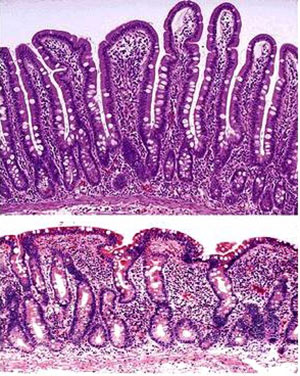

Top: normal mucosa of the duodenum, featuring healthy villi and intact surface enterocytes.

Lower: flattened mucosal surface with the absence of villi and surface enterocyte injury.

上圖:正常的十二指腸粘膜,有健康的手指狀絨毛和完整的腸上皮細胞表面。

下圖:被壓平的粘膜表面,絨毛不復存在,腸上皮細胞表面受損。

消化過的食物被吸收是在小腸內進行,主要是小腸的前兩個部位,十二指腸和空腸。這兩個部位的腸壁是手指狀的突出物,被稱之為絨毛,絨毛之間有腸腺。這些絨毛佈滿腸上皮細胞,主要工作是吸收養分,然後把養分送入血管,滋養身體,因此這些細胞的重要性自是不言而喻。這些細胞誕生於絨毛的基底處,也就是腸腺,然後前進到絨毛的頂端之後脫落,短暫的生命週期就是保持如此的循環,而且十分認真的工作著。

IBD貓腸子的改變,包括明顯的腸結構變化。絨毛形狀改變,變腫變鈍,彼此交纏在一起,吸收養分的表面面積減少。炎性細胞浸潤充滿腸腺,腸壁被壓平。佈滿絨毛的細胞,也就是重要的腸上皮細胞,無法適當的運作。腸道黏膜的健全被破壞,結果是來自腸腔的有毒物質的滲透性和細菌移位都提高了。